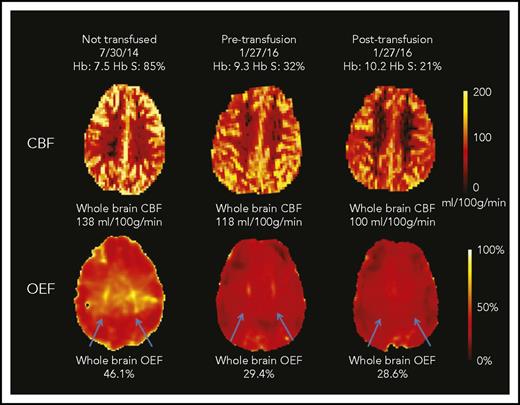

CBF and OEF maps from a child with SCA. This 7-year-old boy underwent an MRI scan before CTT initiation and again before and after an exchange transfusion (only CTT values included in cohort-level analyses). The whole-brain CBF was highest at his first scan (138 mL/100 g per minute). After 17 months of CTT, his pretransfusion CBF was lower than his initial scan (118 mL/100 g per minute; 14% drop) and further decreased after transfusion to 100 mL/100 g per minute (15% drop). The whole-brain OEF was highest at the first scan (46.1%), with dramatic reduction in OEF measured pretransfusion (29.4%; 38% drop) and only modest reduction posttransfusion (28.6%; 3% drop). His OEF maps were also notable for regionally elevated OEF in the deep white matter (blue arrows), which was most prominent before CTT initiation. This peak OEF was still detectable on the pretransfusion scan, although less prominent. After transfusion, the peak OEF region was absent, with restoration of homogeneous OEF across the brain.

Transfusions decreased whole-brain CBF and OEF, without significant change in CMRO2 (Figure 1). Median CBF decreased from 88.0 (IQR, 73.4-110.8) to 82.4 mL/100 g per minute (IQR, 70.9-99.6; P = .005). Median OEF decreased from 34.4% (IQR, 32.1%-38.5%) to 31.2% (IQR, 29.6%-33.8%; P < .001; Table 2). Examples of CBF and OEF maps are shown in Figure 2. Although collectively both CBF and OEF decreased by an average of 9% posttransfusion, the change in CBF only moderately correlated with change in OEF within individuals (ρ = 0.48; P = .05), suggesting that CBF and OEF changes in response to transfusion effects may vary independently. Tissue-segmented (gray vs white matter) CBF, OEF, and CMRO2 demonstrated a similar response to transfusions as whole-brain values (Table 2).

We noted a region of peak OEF within the supraventricular deep white matter in a majority of children with SCA receiving CTT (Figure 2 blue arrows; peak OEF is present pretransfusion and absent posttransfusion). To better define this region and understand the tissue-specific effects of CTT on regional OEF elevation, we averaged all pretransfusion and all posttransfusion OEF maps from the CTT cohort (Figure 4). On the averaged posttransfusion map, this region diminished but remained detectable. To account for hemispheric asymmetries in OEF resulting from vasculopathy or preexisting stroke burden, we evaluated the effect of transfusions on peak OEF within hemispheres, delineated by volume of peak OEF above 36%, 38%, and 40%. We examined 3 thresholds to mitigate a chance association between an arbitrary threshold and transfusion effect. We compared the normalized volume of peak OEF (percentage OEF volume of hemispheric volume) above each threshold before and after transfusion. Peak OEF volumes above each threshold were smaller after transfusion (Figure 4). To evaluate the influence of Hb and Hb S percentage on regionally elevated OEF, we modeled Hb and Hb S percentage as predictors of OEF volumes >40%, finding that Hb was an independent predictor (P < .001), whereas Hb S percentage was not (P = .45). In this model, OEF volume >40% decreased by 3% of total hemispheric volume for every 1-g/dL increase in Hb.